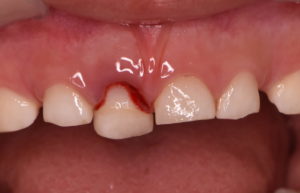

乳歯の形態には異常はなく、打った歯の位置が変わっているため元の位置に整復し、ワイヤーで固定を行います。

脱臼した左上乳中切歯を整復し、両隣の歯とワイヤーで固定します。

脱臼した歯は一度骨から剥がれているため、周囲の骨とくっつくまでこの状態で経過観察をしていきます。

受傷から2週間

脱臼した際に歯の内部の神経・血管に障害が生じるため、内部で充血に伴う歯の変色が生じています。

レントゲン診査でも異常所見はないため、このまま何もせず経過観察を行います。